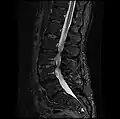

MRI lumbar spine with degeneration, post-hemilaminectomy L4-5 (sagittal T2 FRFSE)

MRI lumbar spine with degeneration, post-hemilaminectomy L4-5 (sagittal T1 FSE)

MRI lumbar spine with degeneration, post-hemilaminectomy L4-5 (sagittal FAST STIR)- MRI lumbar spine post-hemilaminectomy (sagittal T2 FRFSE)